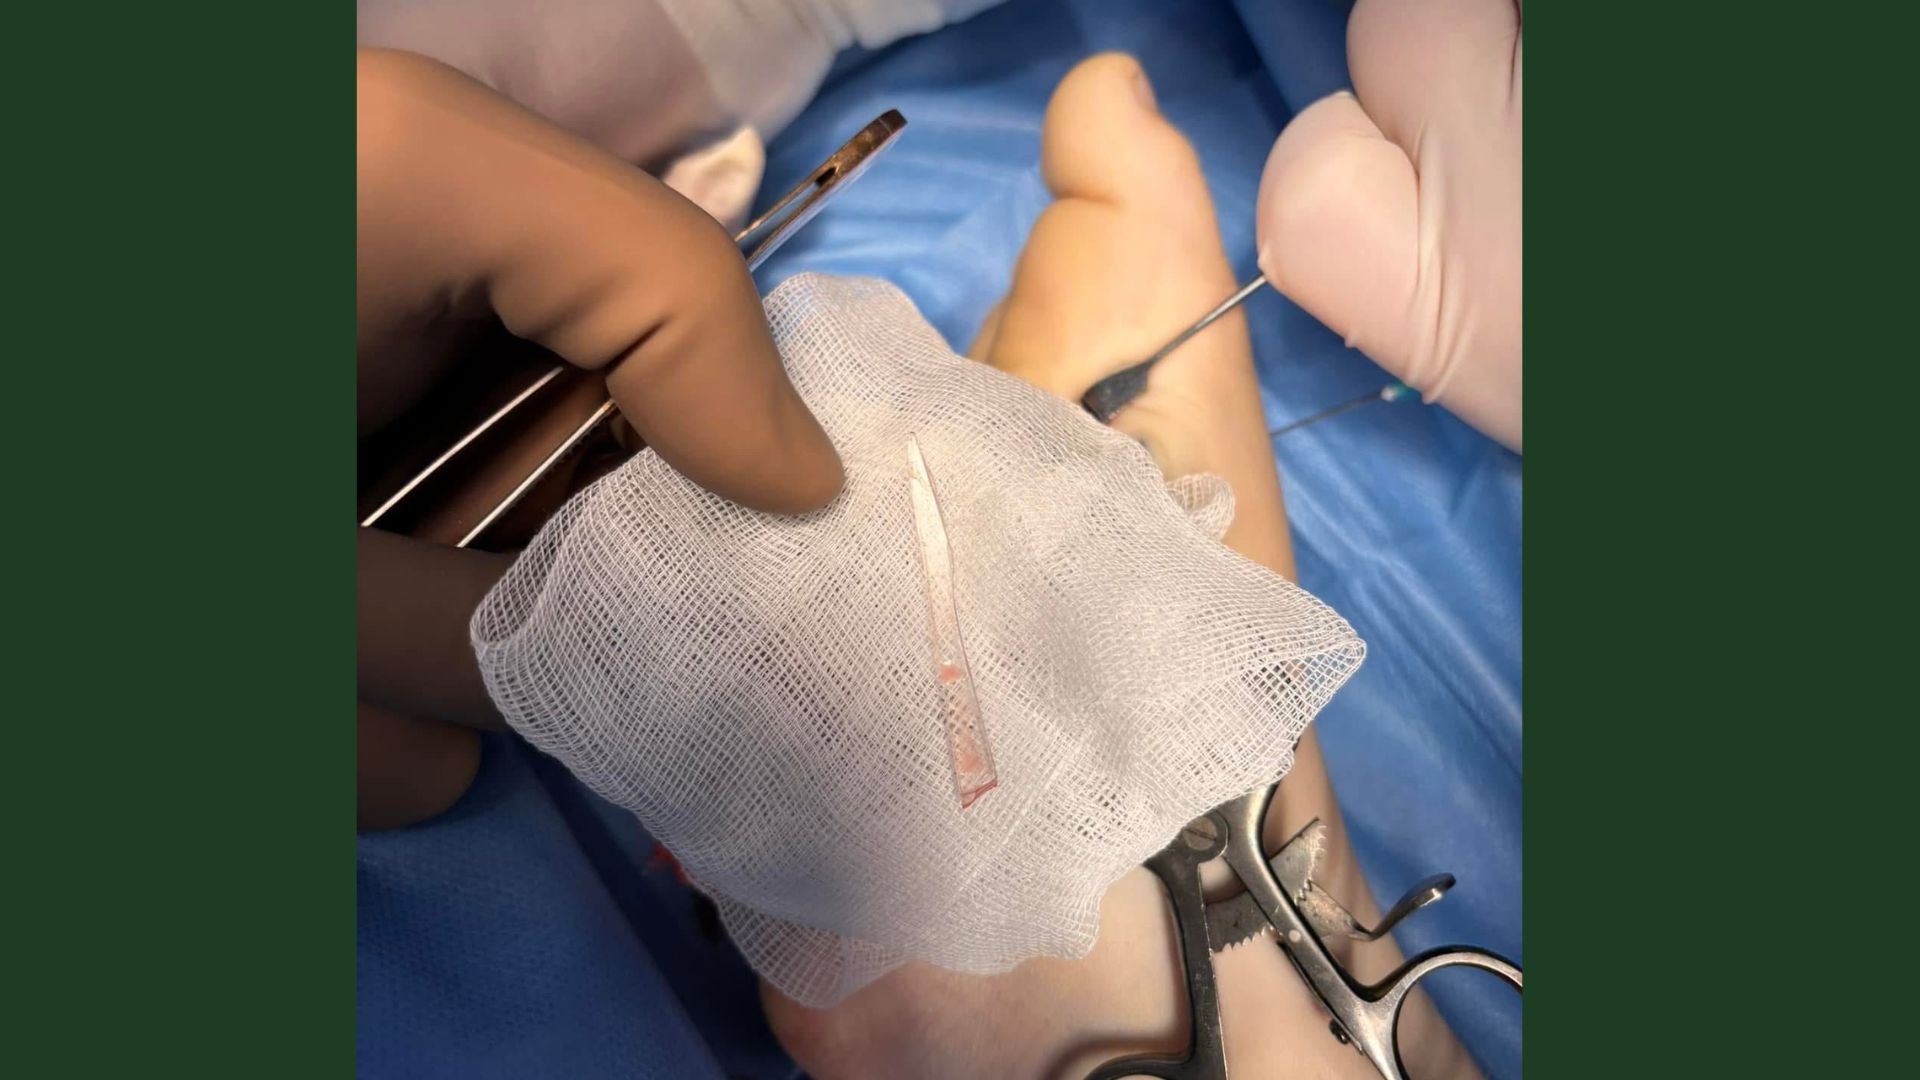

Після клінічного огляду та проведення рентгенологічного обстеження лікарі виявили у стопі стороннє тіло — великий уламок скла. Хірургічне втручання дозволило успішно видалити його без ускладнень.